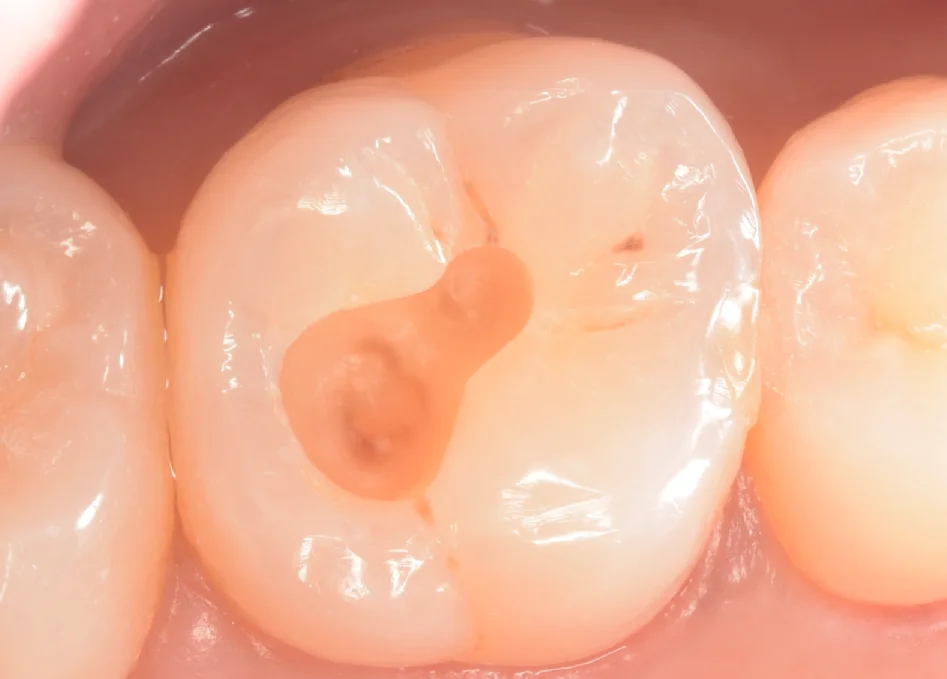

まずは術前からです。

画面中央の白い詰め物の部分が今回治療する部位になります。

数年前に治療を行ったのち、違和感が生じ出したため、再度治療を行うも症状が改善しなかったとのことでした。

見た感じとしては古い詰め物を取り切ることなく治療に入ったように見えますね。